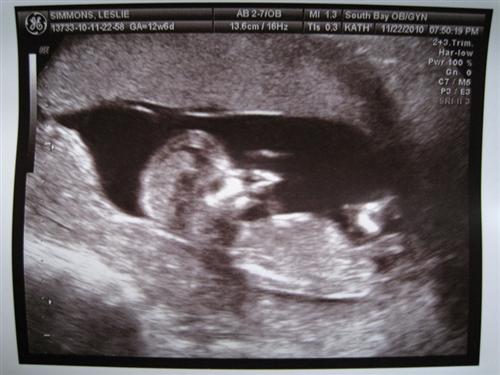

13 weeks with Ultrascreen pics

Baby A was sucking their thumb and Baby B was snuggling Baby A

They definitely share a placenta and there is a very very thin membrane separating them. I have to see the High Risk Dr. in two weeks. So far so good though!